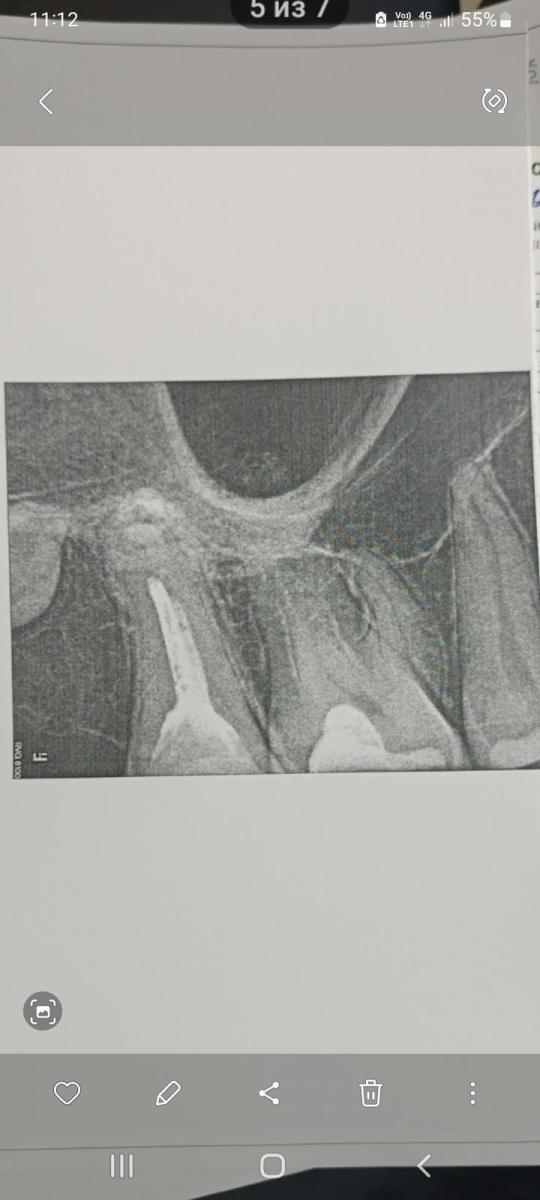

Здравствуйте. Беспокоило пломба на зубе 1.6 забивается пища, пошёл в клинику, врач предложил заменить пломбу, после лечения зуб стал реагировать на холодное, горячее, сладкое, в общем сейчас этой стороной жевать не могу, подскажите почему так?

Юрий Жигурт, добрый день! Сегодня сходил к стоматологу, она сказала, что с момента лечения прошло только 2 недели, а должно месяц и что-то там должно уплотнится, а если не пройдëт, то записываться и приходить снова через 2 недели! Что там должно уплотнится и могут ли болезненные ощущения при жевании пройти сами или всë-таки надо удалять нерв? При осмотре врач стучала молоточком по зубу с разных сторон (Зуб не реагировал), потом прыскала холодным воздухом (зуб тоже не реагировал), затем положила на зуб артикуляционную бумажку (зуб также не реагировал), потом она положила под этот зуб валик из ваты и когда я его прикусил, тогда зуб и заболел((( Когда я предложил ей посмотреть скрин с КТ зубов, доктор сказала, что надо смотреть диск, сказала, что можно принести в любой момент и оставить в регистратуре, а она посмотрит. Приëм ведëт платный стоматолог-парадонтолог со стажем 24 года в гос. стоматологии в платном отделении...